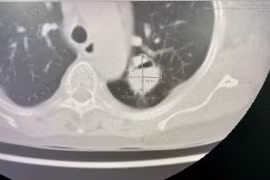

Mới đây, người đàn ông 71 tuổi (TP.HCM) khó thở, mệt mỏi, xây xẩm, choáng váng ho ra 300ml máu đỏ tươi. Sau khi chụp CT cho thấy người đàn ông bị di chứng giãn phế quản tăng sinh mạch máu phế quản sau lao phổi.